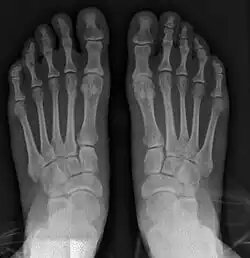

![]() Fig. 8a. Painful hallux valgus and metatarsus primus varus deformity recurrence of left foot after osteotomy surgery | |

- For recurrence correction after osteotomy procedure (Fig. 8)

Late deformity recurrence can happen after osteotomy (bone-breaking) procedures because osteotomy surgeries do not specifically stabilize first metatarsal bone.

For recurrence correction after fusion procedure (Fig. 9) Metatarsus primus varus deformity and pain recurred 6 months after modified Lapidus procedure and it could also be again corrected by the syndesmosis procedure.